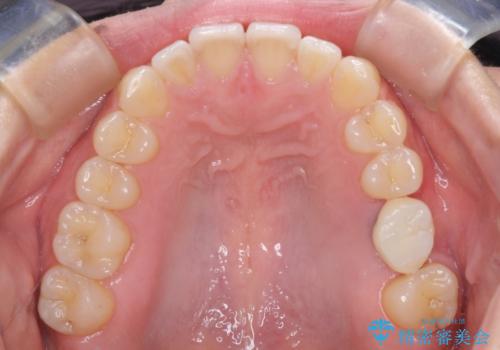

インプラントによる補綴治療とインビザライン矯正

抜歯の上インプラントによる補綴治療を行うこととなりましたが、前歯の叢生も気になるとのことで並行して矯正治療を行うこととしました。

歯列不正は軽微であったので、インビザラインによる矯正治療とし、矯正治療中にインプラント埋入を行う予定としました。

痛みがないので、ボロボロのまま放置していましたが、抜歯後は汚れが溜まりにくくなりスッキリとしたようです。

前歯のデコボコも解消され、ブラッシングが楽になりました。